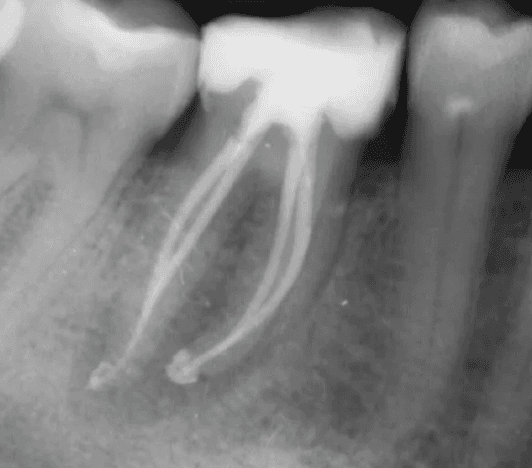

Dr Kreena Patel understands the importance of preserving tooth tissue for the long-term health and strength of your tooth. She uses conservative access and modern instrumentation techniques, including rotary files and microscopic guidance, to treat the tooth precisely and minimally invasively.

KREENA'S CASES